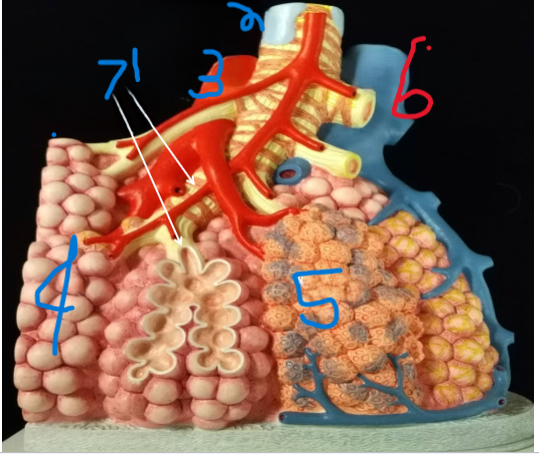

Terminal Bronchiole

What is depicted by #1

Bronchiole with smooth muscle

What is depicted by #2

Pulmonary vein, branch

What is depicted by #3

Alveoli

What is depicted by #4

Pulmonary capillaries

What is depicted by #5

Pulmonary artery, branch

What is depicted by #6

Respiratory Bronchiole

What is depicted by #7